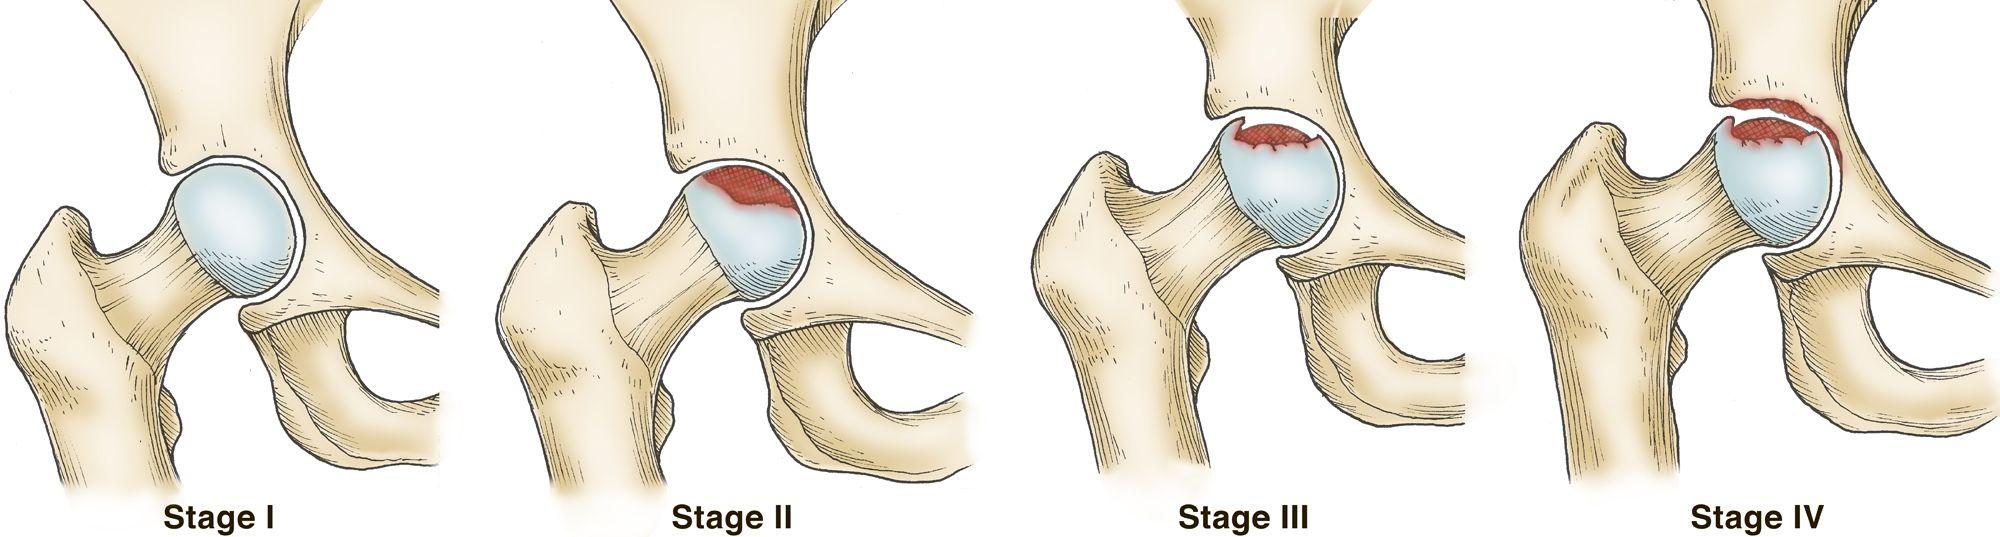

对于保守治疗的患者可能在骨头坏死的一期就可以发现,但是在于,对于使用了金属内固定的手术患者来讲,可能只有进入了股骨头坏死第2期才能够发现的到。所以这些患者在平时的时候要特别留意自己的症状,如果有明显的,髋部的疼痛不适的一些规律性的变化,那么还是要及早的就诊,进行相关的筛查。但是这一点来讲,有时候也是相对比较困难,为什么呢?因为骨折以后周围软组织的损伤以及骨头愈合的过程中,这种疼痛不是都是持续存在的,尤其是已经做了手术的病人,有时候这种组织创伤所造成的慢性疼痛,可能相对还更明显,所以,在判断起来就需要医生来看一下到底,患者现在的不舒服到底是跟手术或者是骨折相关的,还是说头部的坏死相关的。

若患者表现为骨折已愈合,但股骨头缺血性坏死,在股骨头坏死尚未严重变形前,可先保持正常生活,防止过多运动和负重。1期和2期的股骨头坏死都可以叫做早期的股骨头坏死,早期的股骨头坏死在治疗方面是有一定的方法和建议的。骨头坏死以后,出现局部疼痛是一方面,但是由于坏死以后区域的强度下降造成局部的塌陷,形成关节面的不光滑,就会使得髋关节的关节面磨损增加,形成明显的骨性关节炎,就是股骨头坏死远期的一个非常不好的一个并发症,是造成患者进行手术的一个非常重要的原因。

所以对于早期股骨头坏死,也就是说骨头没有明显变形之前,我们治疗的目的就是延缓它的一个病情进展,使得股骨头坏死以后的一个股骨头变形,往后推或者是尽量不要发生。其实在生活中有一少部分人,会一直保持骨头的形态是完好的,即使有骨坏死,但是没有形成明显的骨关节炎的症状,这个时候他也可以一辈子保守治疗,不进行人工关节置换。